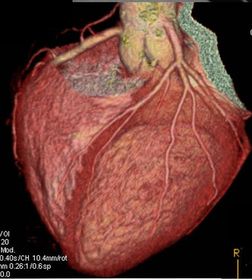

Cateterismo Cardiaco

Anatomía y extensión Choque cardiogénico No mejora con medicamentos Congestión/Edema pulmón Ventriculo derecho Inestabilidad hemodinámica o eléctrica Alto riesgo (Inhibición de glicoproteina IIb/IIIa) TIMI < 3

Caption: : http://sicimedical.com/index.php/informacion-para-pacientes/afectacion-de-las-arterias-del-corazon/que-es-un-cateterismo-cardiaco/